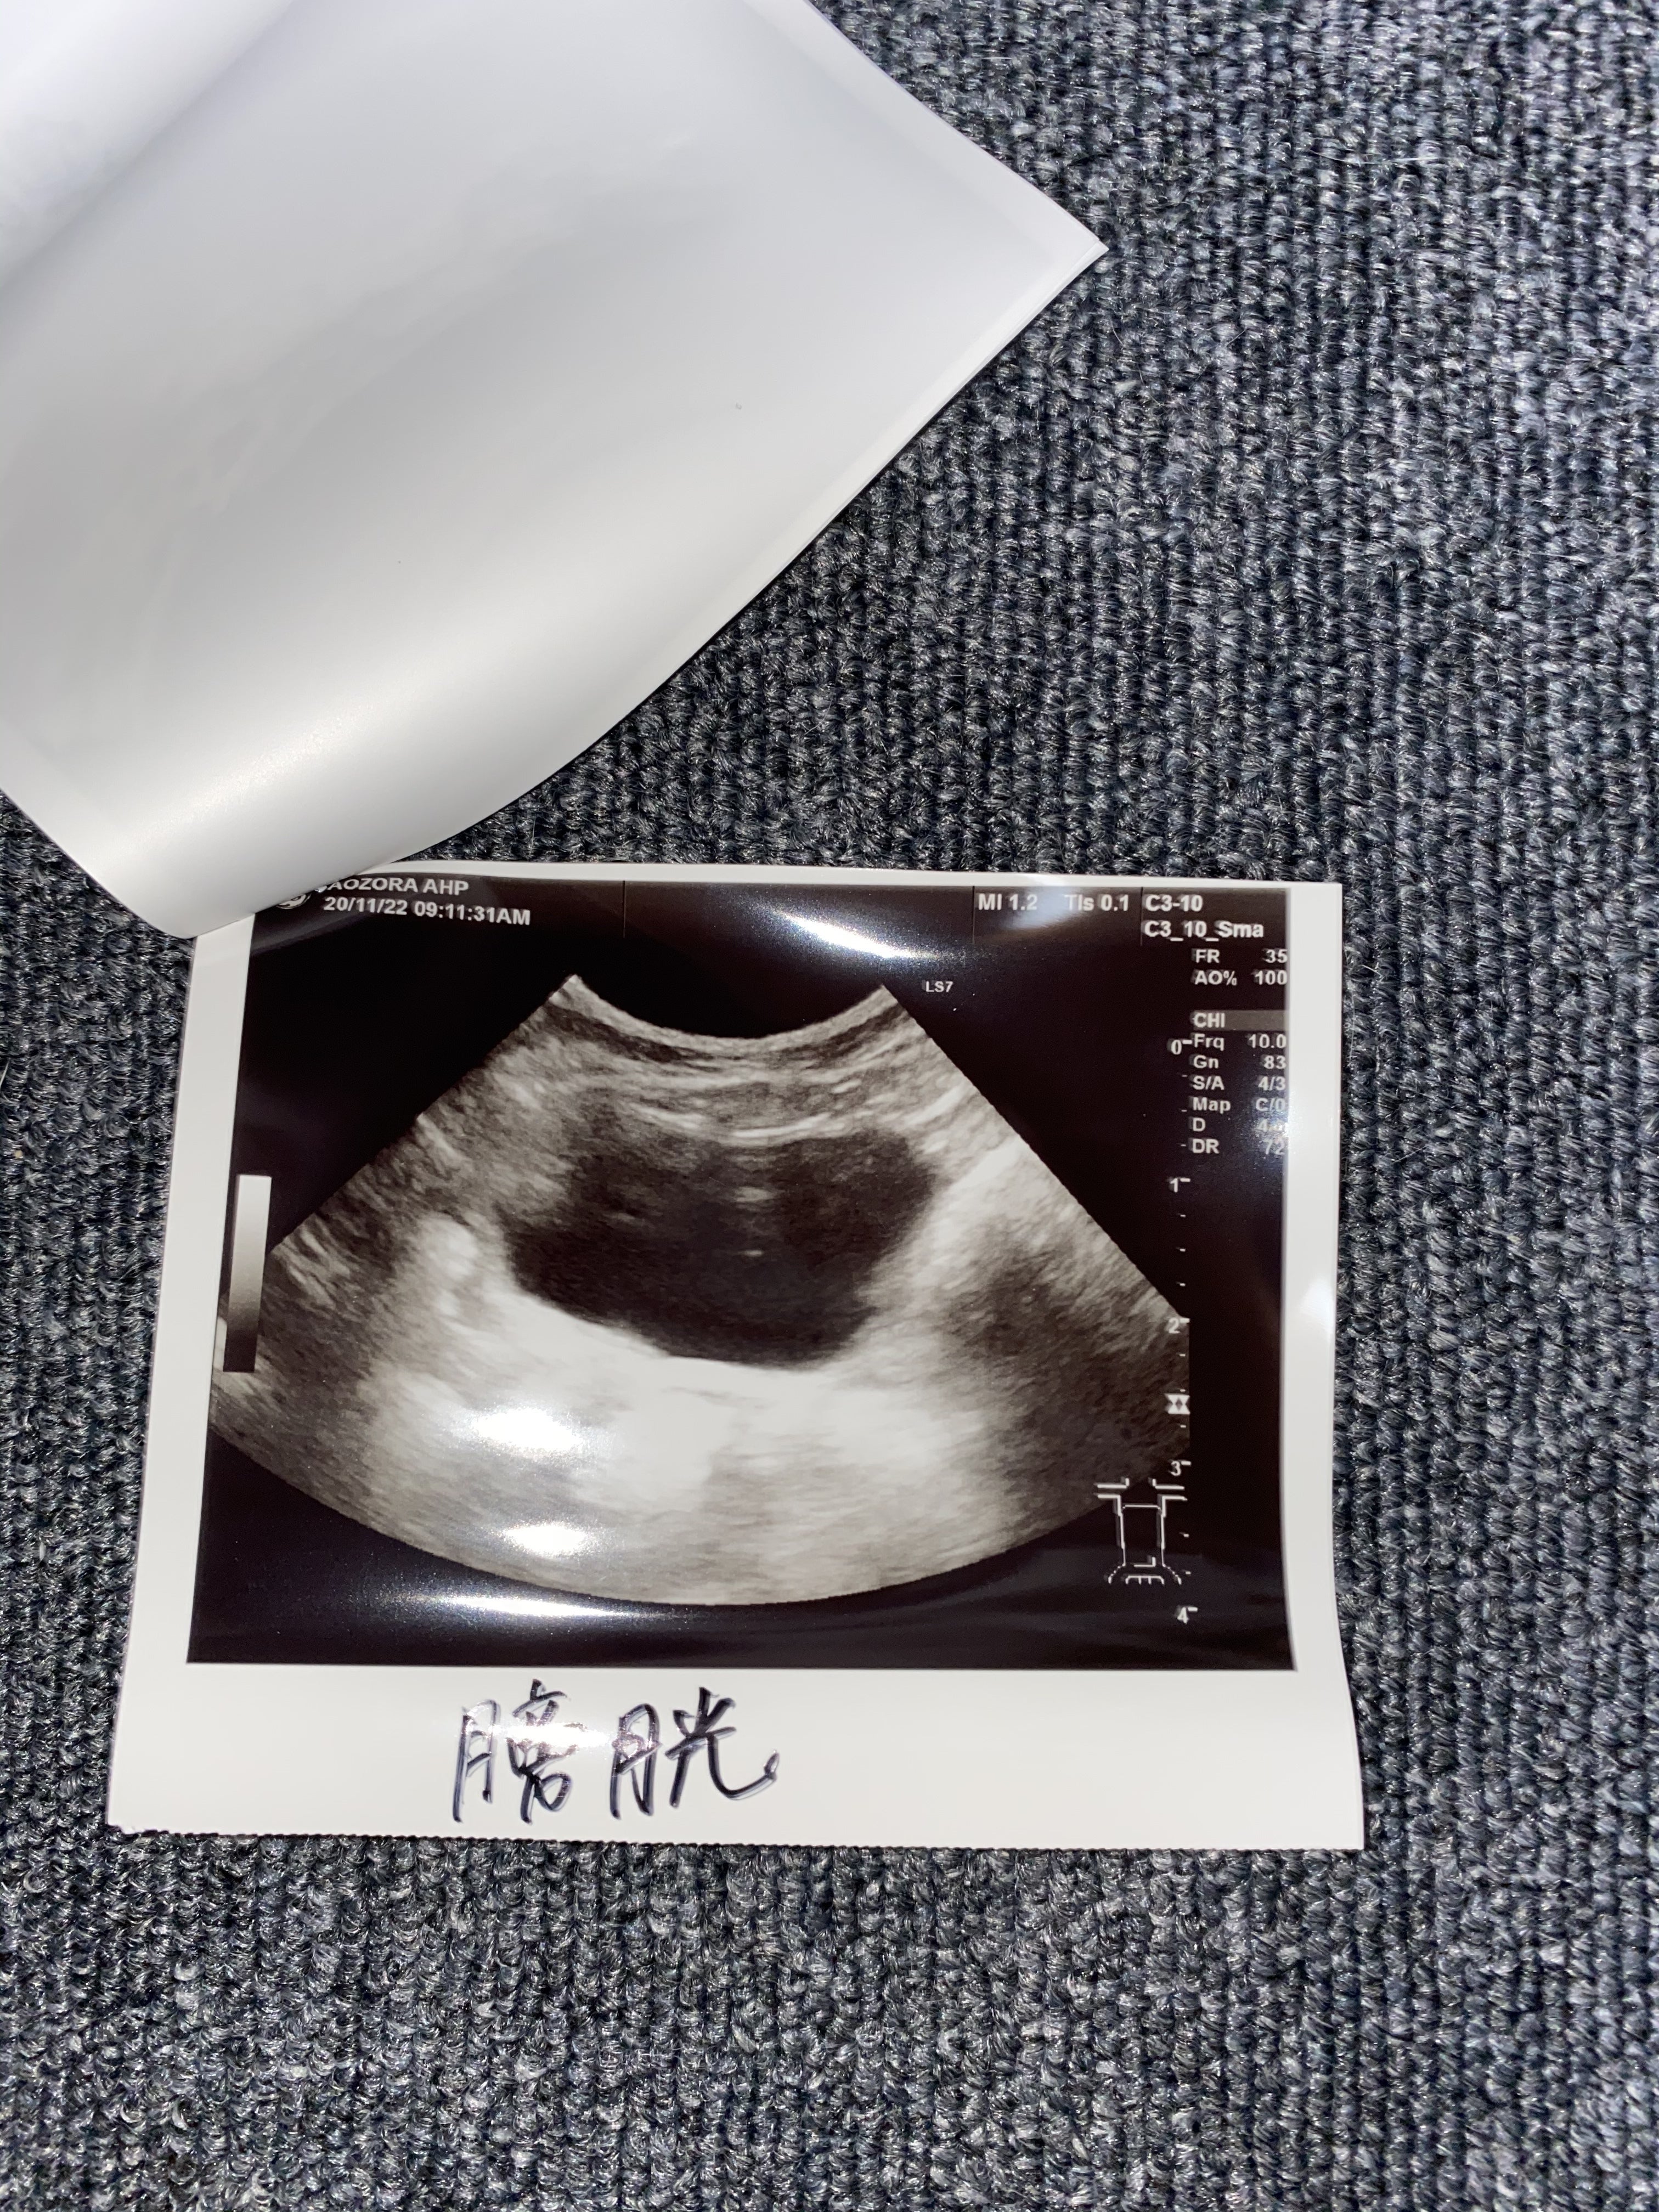

エコー検査も綺麗で問題ないそうです。